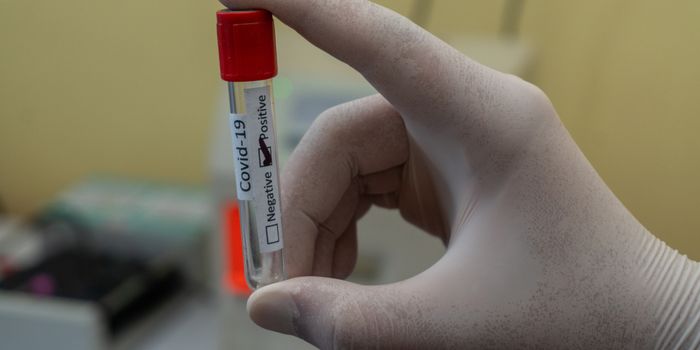

MAR 28, 2023TechnologyOne particularly tricky part of the COVID-19 pandemic was being able to distinguish between COVID-19 infection and other ...